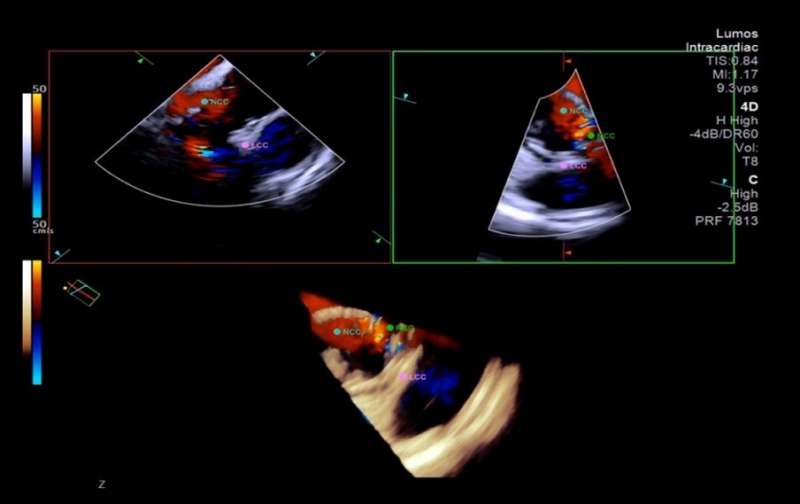

중앙대광명병원(병원장 정용훈)은 국내 최초로 4D(4차원) 심장내 초음파(ICE)를 활용한 경피적 대동맥판막 삽입술(TAVI)을 성공적으로 마쳤다고 26일 밝혔다.

순환기내과 임홍의 교수와 조준환 교수는 이달 13일 국내 최초로 4D 심장내 초음파를 이용한 경피적 대동맥판막 삽입술 2케이스를 성공적으로 실시했다.

심장내 초음파 분야 최고 권위자인 임홍의 교수는 “입체적 영상을 실시간으로 활용하면 시술자는 심장과 시술 장치 구조를 보다 정확하게 파악할 수 있어 시술 효율성과 안전성을 최대로 높일 수 있다”고 말했다.

이어 “특히 정밀한 기술이 요구되는 경피적 대동맥판막 삽입술과 같은 고난도 시술에서 그 활용도가 더욱 기대된다”고 밝혔다.

한편, TAVI는 허벅지 동맥을 따라 심장판막까지 풍선을 진입시킨 뒤 좁아진 판막 부위에서 풍선을 부풀려 그물망 형태 인공판막 스텐트를 삽입해 기존 판막을 대체하는 시술이다. 4D 심장내 초음파는 심장 내부 구조를 실시간으로 정밀하게 보여주는 고해상도 영상 기술이다.